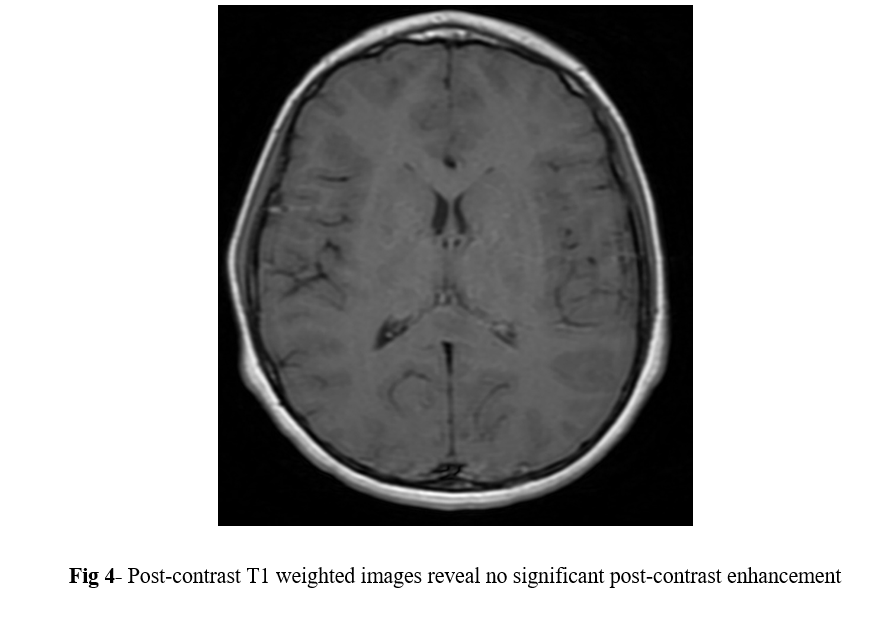

MRI of the brain with contrast was performed using 1.5 tesla scanner (GE Medical System). An oval well-circumscribed lesion was noted in the splenium of the corpus callosum in the midline (Figure 1). The lesion displayed restricted diffusion with low ADC values (Figures 2 and 3). No evidence of mass effect or perifocal edema was seen. No evidence of abnormal post-contrast enhancement was noted (Figure 4). No lesions are seen in the periventricular white matter and in the subcortical U fibers. In view of the clinical history and morphology of the lesion was read as reversible splenial lesion syndrome (RESLES). The differential diagnosis that were considered included ADEM, multiple sclerosis, encephalitis and glial tumor.

Figure 4